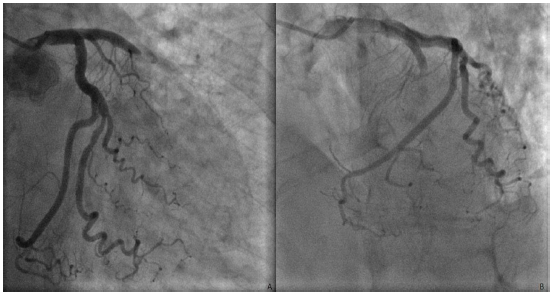

Em seguida, a paciente foi imediatamente encaminhada para a hemodinâmica, apresentando apenas a alteração demonstrada nas seguintes incidências: